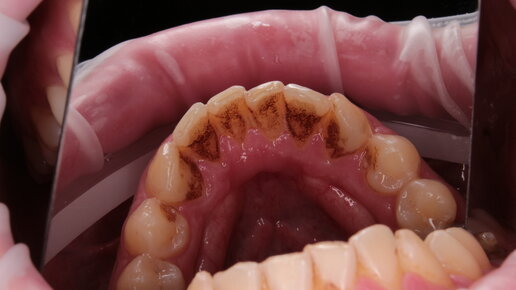

Как убрать черный налет с зубов?

Черный налет появляется в результате скоплений зубных отложений. Можно ли убрать темные пятна с эмали самостоятельно или лучше сразу отправиться к специалисту? Как такой налет убирают в стоматологии? Ответы эти вопросы ищите в статье...

Как убрать черный налет на зубах? Полезные советы от врача

Черный налет на зубах – очень неприятная проблема, которая портит красоту улыбки, заставляет стесняться и вызывает много комплексов. Вся беда заключается в том, что от появления такого вида налета не застрахован никто. Поэтому сегодня мы расскажем не только обо всех возможных методах, которые помогут быстро его удалить, но и о причинах его появления. Уверены, вы удивитесь, насколько некоторые из них неожиданные. ТОП-6 причин почернения зубов Для многих это становится открытием, но даже если вы ежедневно чистите зубы, то на них может появиться черный налет или пятна...